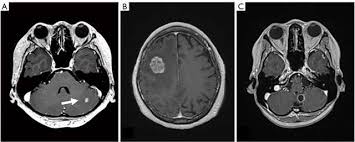

Advanced Breast Cancer Novartis Uk from www.novartis.co.uk It will also be necessary for the patient to remain vigilant for signs of metastatic breast cancer. Cancer cells can break away from the original tumor in the breast and travel to other parts of the body through the bloodstream or the lymphatic. Breast cancer is among the most typical kinds of cancer in american women, accounting for about 30 percent of new cancer cases in 2017. With metastatic breast cancer, the goal of treatment is to shrink or weaken the cancer, manage your symptoms and side effects and prevent the cancer from spreading further. Metastatic breast cancer, also called stage iv, is breast cancer that has spread to another part of the body, most commonly the liver, brain, bones or what are the symptoms? Metastatic breast cancer, also referred to as metastases, advanced breast cancer, secondary tumors, secondaries or stage iv breast cancer, is a stage of breast cancer where the breast cancer cells have spread to distant sites beyond the axillary lymph nodes. These are the warning signs to look for. Metastatic breast cancer is stage 4 (iv), or advanced breast cancer.

What are the different types of metastatic breast cancer? It is also called stage iv (4) breast cancer. What is the prognosis of breast cancer? Metastatic breast cancer occurs when the cancer spreads from the breast to another part of the body. Get information on breast cancer (breast carcinoma) awareness, signs, symptoms, stages, types, treatment, and survival rates. When does metastatic breast cancer appear? Breast cancer is also classified according to other characteristics. Breast cancer is a deadly condition that affects women. Symptoms and early signs of breast cancer in females. What is stage iv breast cancer and what are the survival rates for women. They help describe your cancer. Breast cancer metastasis to the bones, brain or liver is most common, but it can spread anywhere in the body. With bone metastasis, the most common symptom of breast cancer that has.

Breast Cancer Recurrence Breast Cancer Surgery Melbourne Vic from www.melbournebreastcancersurgery.com.au Staging of metastatic or recurrent breast cancer. Signs of cancer in the brain include headaches, seizures, vision changes, and dizziness. Sign up for our weekly newsletter. What's new in breast cancer research? Many of these signs are uncommon, but are mentioned. When does metastatic breast cancer appear? It will also be important for the patient to remain vigilant for signs of breast cancer metastasis. However, in other cases, the metastasis of breast cancer is found months or even years after the initial treatment.

When does metastatic breast cancer appear? This term refers to women who are stage iv at the initial diagnosis. What's new in breast cancer research? The subtype is based on biomarkers. I always encourage a patient with a history of breast cancer to call us if she has a. General signs that breast cancer has spread to other organs and become metastatic include the following what is the survival rate for metastatic breast cancers? We also list some of the symptoms which can occur due to complications of metastatic breast cancer. Metastatic breast cancer, also called stage iv, is breast cancer that has spread to another part of the body, most commonly the liver, brain, bones or what are the symptoms? In most cases, it arises months or years after a person has completed treatment more from michigan: Get information on breast cancer (breast carcinoma) awareness, signs, symptoms, stages, types, treatment, and survival rates. The word metastatic refers to a higher or lower amount of a particular substance may be a sign of disease. Sometimes people with metastatic breast cancer do not have any of these changes. What is stage 0 breast cancer?